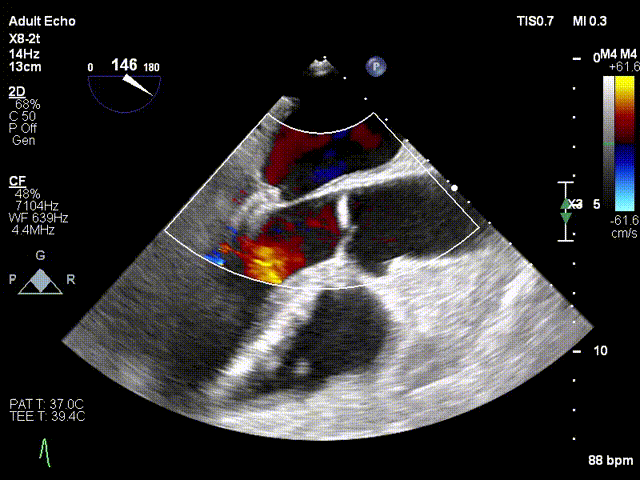

经食道超声显示(术前):二尖瓣P2脱垂,反流束主要来源于A2/P2区域,前叶长度28mm,后叶长度14mm,脱垂宽度为11m,脱垂高度为9.5mm,量4+。

术前TEE显示二尖瓣重度反流,反流主要来源于A2/P2区